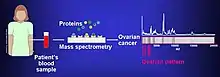

Biomarkers of cancer have been found by mass spectrometry based proteomic analyses. The use of proteomics or the study of the proteome is a step forward in personalized medicine to tailor drug cocktails to the patient's specific proteomic and genomic profile.[8] The analysis of ovarian cancer cell lines showed that putative biomarkers for ovarian cancer include "α-enolase (ENOA), elongation factor Tu, mitochondrial (EFTU), glyceraldehyde-3-phosphate dehydrogenase (G3P), stress-70 protein, mitochondrial (GRP75), apolipoprotein A-1 (APOA1), peroxiredoxin (PRDX2) and annexin A (ANXA)".[9]

Mass spectrometry is one of the key methods to study the proteome.[22] Some important mass spectrometry methods include Orbitrap Mass Spectrometry, MALDI (Matrix Assisted Laser Desorption/Ionization), and ESI (Electrospray Ionization). Peptide mass fingerprinting identifies a protein by cleaving it into short peptides and then deduces the protein's identity by matching the observed peptide masses against a sequence database. Tandem mass spectrometry, on the other hand, can get sequence information from individual peptides by isolating them, colliding them with a non-reactive gas, and then cataloguing the fragment ions produced.[23]